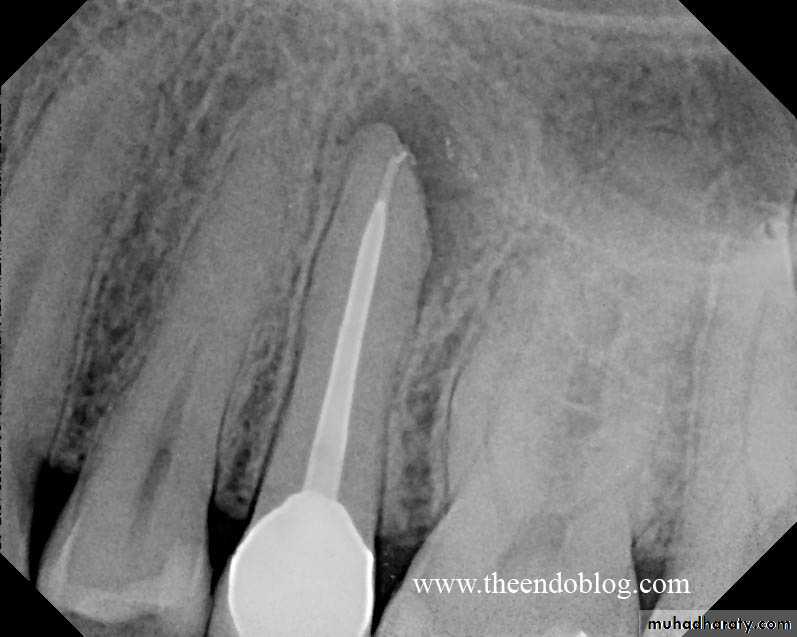

Radiographic features:

Initially, No radiographic change.

With progression, slight widening of PDL, lamina dura may become less defined.Histopathological features:

Most lesions are discovered on routine radiographic examination.A well-defined radiolucency of bone apical to the offending tooth. Loss of the apical lamina dura.

The lesion may be circumscribed or ill defined.